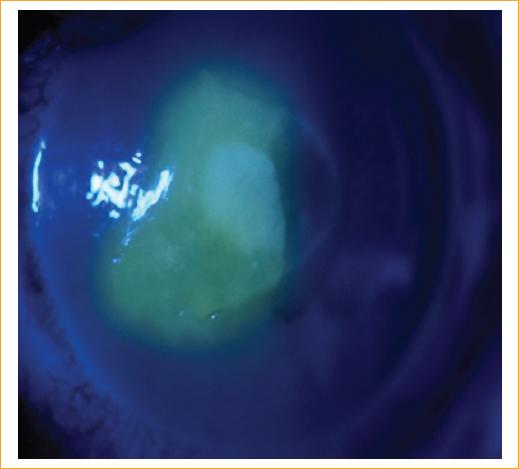

Varón de 45 años que consulta al servicio de urgencias por un cuadro clínico de 3 días de evolución consistente en dolor, ojo rojo, fotofobia y sensación de cuerpo extraño en el ojo izquierdo posterior al lavado de la cara con agua de tanque en un área rural. El paciente refiere estar aplicando gotas de lágrimas, sin mejoría de la sintomatología. Al examen oftalmológico de ingreso presenta una agudeza visual en el ojo derecho de 20/20 y en el ojo izquierdo de 20/400. En la biomicroscopia, el segmento anterior del ojo derecho está sano. En el ojo izquierdo se evidencia una importante hiperemia conjuntival con un defecto epitelial central de 5 × 5 mm que compromete el eje visual, con infiltrado intraestomal de 2 × 2 mm, de bordes plumosos, con lesiones satélite, infiltración en anillo y edema estromal perilesional, con tinción positiva a la fluoresceína (Figs. 1 y 2); el resto del segmento anterior del ojo izquierdo es normal. La presión intraocular del ojo derecho es de 12 mmHg y la del ojo izquierdo no se determina. La fundoscopia indirecta de ambos ojos es normal. Posteriormente se realiza raspado del absceso con hoja de bisturí del n.º 15, que se reserva en tubo de ensayo y es llevado al laboratorio de patología para ser examinado por el patólogo en el microscopio con tinción de hematoxilina-eosina.

Figura 2 Foto clínica del ojo izquierdo, con tinción positiva a la fluoresceína con luz azul de cobalto difusa.